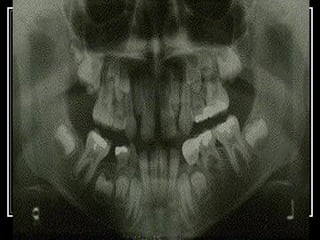

   This is a radiograph of a similar situation

showing the missing mandibular right

second primary molar

Again, is this a situation requiring

placement of a space maintainer?

   Yes; a space maintainer is indicated